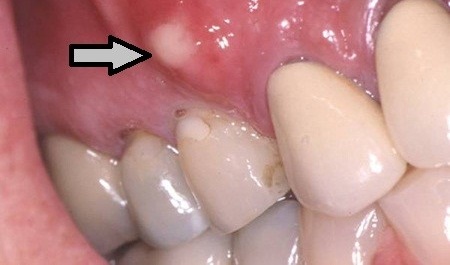

Dişte bulunan sinirlerde travma, bakteri ya da kimyasal tahrişlerin söz konusu olması sonucunda canlılığın yitirilmesi, enfeksiyonun dişin kök ucundan çevre dokulara yayılmaya başlamasına yol açar. İlerleyen süreç içerisinde dişin kök ucu çevresinde bulunan kemiğin üzerinde bölgesel bir iltihap toplanması söz konusu olur. Tıp dünyasında dişte ortaya çıkan bu duruma ilişkin olarak diş apsesi tanımlaması gerçekleştirilir. Söz konusu iltihap oluşumu zaman içerisinde diş kökünün tutunduğu kemik üzerinde erimeye neden olarak, kendisine yol açar ve diş eti üzerinde içerisinde ‘irin’ bulunan bir şişliğin meydana gelmesine sebep olur. Eğer dişte meydana gelen sorunun bu aşamaya gelmesine engel olunmaz ise hastanın diş kaybı ile karşı karşıya kalması mümkün olur.

- Diş apsesi belirtileri çerçevesinde apsenin ilerleyen süreçte dokuların zayıflamış noktalarından kendisine yol açarak, ağız içerisine ya da ağız dışına akış gerçekleştirebilir. Bu durumda ağız içerisinde kötü koku ve tat oluşumunun yaşanmasına neden olur. Ancak bu aşamada mevcut ağrı semptomunda hafifleme gözlemlenir.